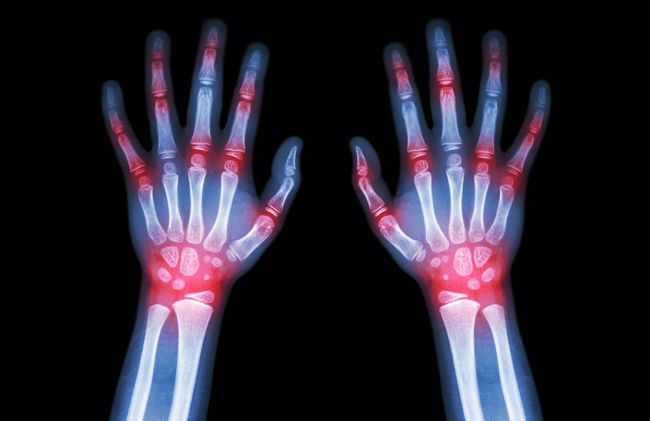

La artritis es una enfermedad del sistema inmune que afecta las articulaciones produciendo inflamación crónica y dolor.

En el caso de la artritis el cuerpo ataca especialmente a las articulaciones. El ataque a las articulaciones, desarrolla la inflamación y el dolor de esta enfermedad.

De acuerdo a un estudio en Autoimmunity, en las articulaciones afectadas por la artritis sientes al comienzo solo molestias y ardor. La artritis evoluciona con un dolor punzante, quemante, agudo e insoportable.

Es común que sientas la presencia de líquido e hinchazón en articulaciones. La inflamación en personas con artritis ocurre en muñecas, codos, rodilla y tobillo.

La inflamación afecta la movilidad de tu mano, muñeca y dedos. Se presenta en ambos lados del cuerpo al mismo tiempo o alternadamente.

La inflamación a largo plazo, como en la artritis destruye el tejido, en este caso el cartílago. A medida que las articulaciones se afectan, se desgastan los tejidos óseos causando las deformaciones.